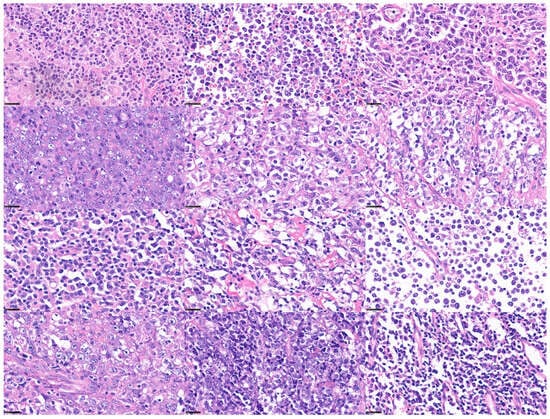

Lymphoid neoplasms originate from B lymphocytes and T lymphocytes. They include precursor B- and T-cell lymphoid neoplasms (acute lymphoblastic leukemia/lymphoma), mature B-cell neoplasms, such as chronic lymphocytic leukemia, follicular lymphoma, diffuse large B-cell lymphoma, and multiple myeloma; mature T or natural killer (NK) cell neoplasms, such as peripheral T-cell lymphoma (PTCL); and Hodgkin lymphoma. Hodgkin lymphoma is characterized by a mixed inflammatory cell background that includes a minority of neoplastic cells, known as Reed–Sternberg cells, and their variants, which are derived from germinal or post-germinal centers [1,5]. Figure 1 and Figure 2 show a summarized version of the classification of hematopoietic neoplasms and characteristic histological images.

Figure 2. Histological images of lymphoma subtypes (Hematoxylin and Eosin staining; original magnification 400×). Chronic myeloid leukemia (CML), acute myeloid leukemia (AML), B lymphoblastic lymphoma (B-LBL), chronic lymphocytic leukemia/small lymphocytic lymphoma (CLL/SLL), lymphoplasmacytic lymphoma (LPL), plasma cell myeloma (PCM), mucosa-associated lymphoid tissue (MALT) lymphoma, follicular lymphoma (FL), mantle cell lymphoma (MCL), Burkitt lymphoma (BL), diffuse large B-cell lymphoma (DLBCL) with MYC rearrangement (MYC-R+), high-grade B-cell lymphoma with MYC, BCL2, and BCL6 rearrangement (triple-hit lymphoma (THL)), classical Hodgkin lymphoma (cHL), peripheral T-cell lymphoma (PTCL), not otherwise specified (NOS), and monomorphic epitheliotropic intestinal T-cell lymphoma (MEITL).